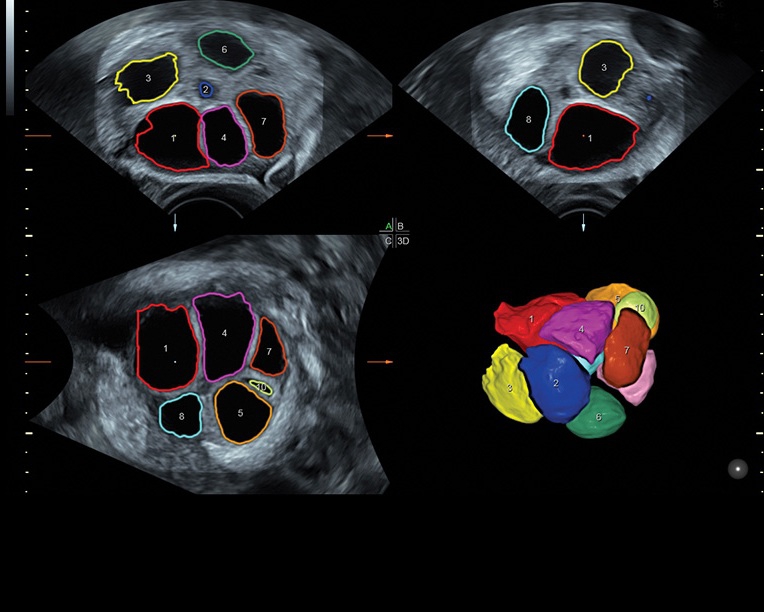

• Сложные инструменты для оценки качества плода: Сканер оснащен инновационными инструментами, позволяющими проводить детальную оценку состояния плода, включая его сердечную деятельность, анатомию и кровоток.

• Программа для исследований сердца плода с возможностью цветовых допплеровских и ангиографических исследований на основе анализа пространственно-временной корреляции изображений (STIС)

• Программное обеспечение для исследования сердца плода в режиме 3D/4D (быстрый доступ к плоскостям сканирования) по рекомендациям ISUOG

• VOCAL ™, SonoAVC (SonoAVC follicle, SonoAVCantral).SonoVCAD labor - программное обеспечение для исследования во втором периоде родов